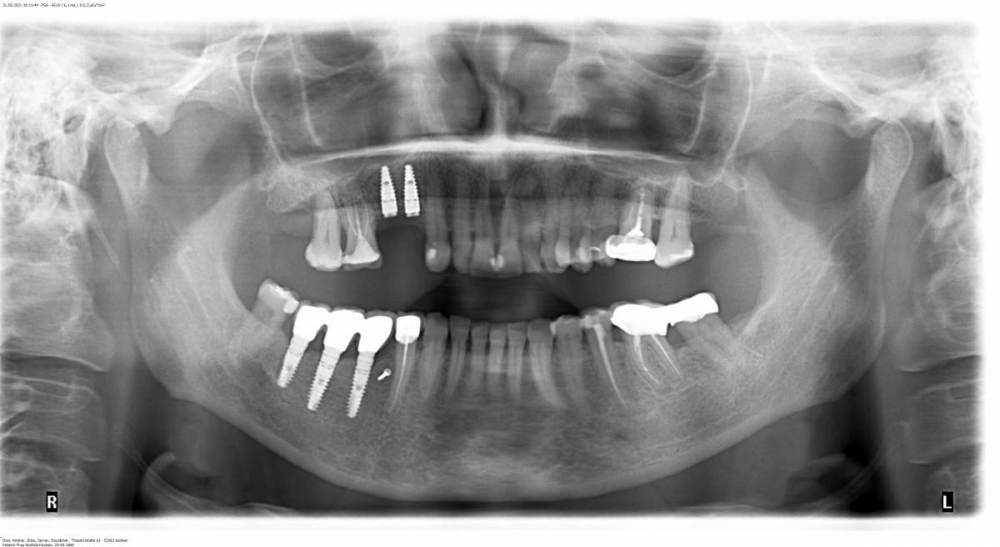

Анжела 66 Опубликовано 26 июля, 2021 Поделиться Опубликовано 26 июля, 2021 Добрый день, уважаемые доктора! Очень прошу вашего совета по вопросу спасения ( если это вообще возможно) импланта 47. Три рядом стоящие импланты были имплантированы 10 лет назад в немецкой клинике професора Кюри с наращиванием кости по им разработанной тунельной технологии. Все это время , 9 лет, ежегодно посещала клинику для контроля имплантов и профессиональной чистки. Где-то месяц назад появилась отечность, покраснение и (при использовании интердентальных щеток) кровоточивость. Так как 31.05.2021 была проведена имплантация верхних зубов другим имплантологом, обратилась, конечно же, к нему. Чистка и локальное лечение в течении 2-х недель ( 4 посещения врача) особого улучшения не принесли. Теперь врач обратил внимание на темную подозрительную линию идущую вдоль всего импланта 47. Несмотря ны двадцатилетний стаж , сказал, что не знает, что это за линия. Его последующие действия: если ситуация не улучшится, отек и покраснение не уйдет, проведет открытую хирургическую чистку и посмотрит , что же там. Если и это не узменит ситуацию, удаление импланта. Другой врач-стоматолог, посмотрев рентген, сказал, что это инфекция, расположенная очень глубоко и , самое главное, не типично и шансов спасти почти нет. При зондировании глубина корманов до 3 мм. Резорбции кости вроде нет. Очень хотелось бы знать ваше мнение и возможный в данной ситуации алгоритм действий. Стоит ли обратиться за возможной помощью к создателю этой конструкции профессору Кюри или уже ничего и никто не поможет? С уважением, Анжела Ссылка на комментарий

Анжела 66 Опубликовано 26 июля, 2021 Автор Поделиться Опубликовано 26 июля, 2021 1 час назад, It'sGeorgy сказал: По снимку проблем вообще не видно. Думаю очный осмотр профессора Кури - лучший из вариантов. Может быть , вот так будет лучше видно. Потемнение вдоль винта импланта 7-ки. Ссылка на комментарий

Карен Аванесов Опубликовано 26 июля, 2021 Поделиться Опубликовано 26 июля, 2021 Если гарантии, которые Вам дали в немецкой клинике в силе, обращайтесь к ним, если нет, в России, достаточное количество и учеников Хури и даже тех специалистов которые сделают лучше. На снимке или фонит металл или периимплантит, учитывая Ваши жалобы. Ссылка на комментарий

It'sGeorgy Опубликовано 26 июля, 2021 Поделиться Опубликовано 26 июля, 2021 (изменено) 6 часов назад, Анжела 66 сказал: Где-то месяц назад появилась отечность, покраснение и (при использовании интердентальных щеток) кровоточивость конкретно в области имплантата 4.7? 6 часов назад, Анжела 66 сказал: При зондировании глубина корманов до 3 мм. Резорбции кости вроде нет. десна толщиной 3мм(если вы это имели ввиду) в области имплантата - норма 5 часов назад, Анжела 66 сказал: Потемнение вдоль винта импланта 7-ки. как выше отметил @Карен Аванесов , это либо признаки периимплантита, либо фонит имплантат(такое бывает очень часто). 6 часов назад, Анжела 66 сказал: Стоит ли обратиться за возможной помощью к создателю этой конструкции профессору Кюри или уже ничего и никто не поможет? 6 часов назад, It'sGeorgy сказал: Думаю очный осмотр профессора Кури - лучший из вариантов. Изменено 26 июля, 2021 пользователем It'sGeorgy Ссылка на комментарий

Irouil Опубликовано 27 июля, 2021 Поделиться Опубликовано 27 июля, 2021 Конечно, лучше всегда продолжать лечение у того специалиста, у которого оно было начато. Тем не менее, я бы посоветовал сделать компьютерную томограмму и прицельный снимок интересующей области, для начала. На предоставленном снимке явных причин для описанных Вами жалоб нет, поэтому нужно дообследоваться Ссылка на комментарий